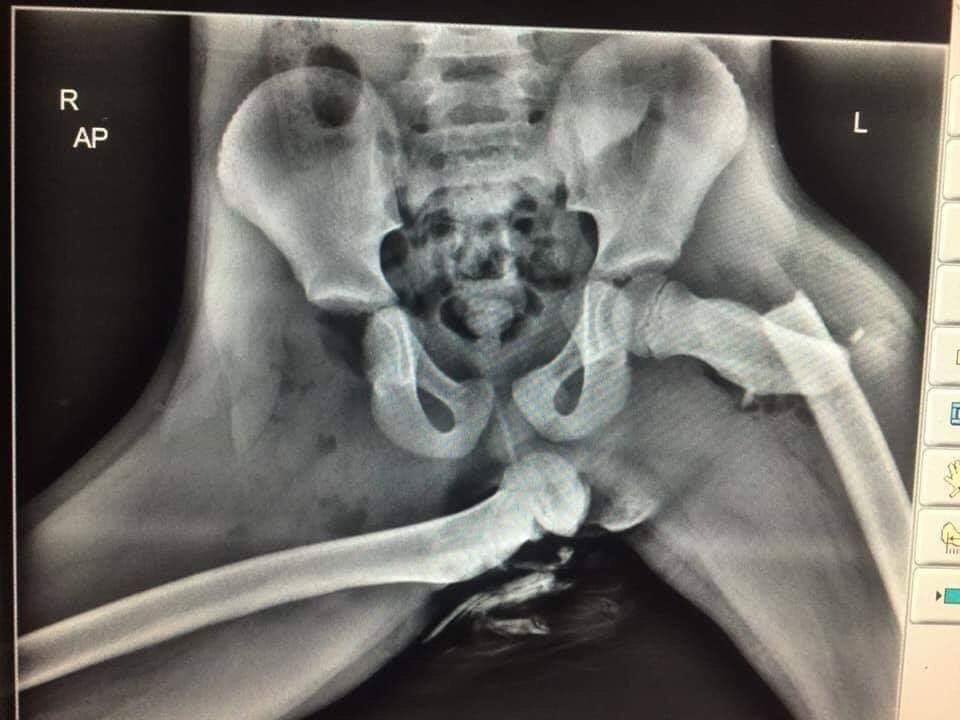

Snimak rendgena pokazuje ishod udesa u kojem je mlada žena iz Velsa držala svoje noge na armaturnoj tabli. Jedna bedrena kost je slomljena, jedan kuk je polomljen, a drugi dislociran. Dakle, uspravan položaj sedenja, noge na podu, i naravno vezan sigurnosni pojas omogućavaju automobilu da vas zaštiti što više može u slučaju nezgode.